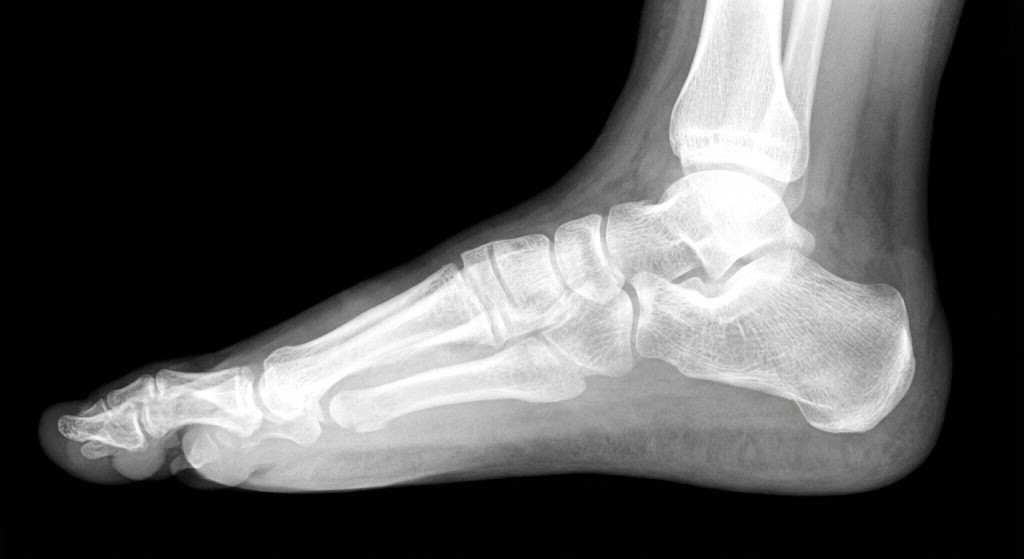

2. الأشعة السينية (X-Ray)

في الحالات اللي تحتاج تقييم أدق، د. نبيل بيطلب أشعة على القدم في وضعين:

- أشعة واقف (Weight-bearing): الطفل بيقف على القدم والأشعة بتوضح شكل العظام تحت الضغط.

- أشعة جانبية: بتقيس زاوية القوس بدقة.